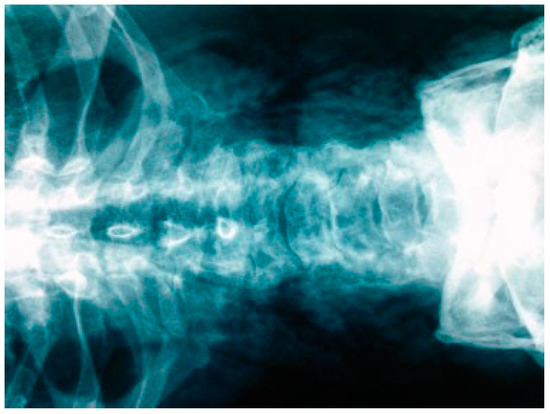

Acute Hyponasality (Closed Rhinolalia) and Craniomaxillofacial Fracture Suggest the Coexistence of Retropharyngeal Emphysema and Pneumomediastinum

Case Report